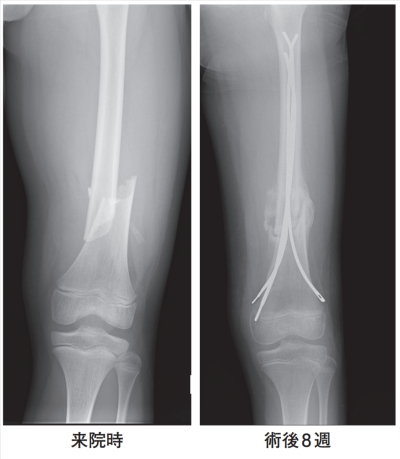

身長 150 cm、体重 45 kg。歩行は不能で左大腿部に腫脹を認めた。左大腿骨エックス線写真で大腿骨骨幹部骨折を認め、受傷翌日、観血的骨接合術が行われた。術後経過は順調で、術後 8 週が経過し、左大腿部に異常所見を認めない。来院時と術後 8 週の左大腿骨エックス線写真を別に示す。

術後 8 週の骨折部の状態で正しいのはどれか。